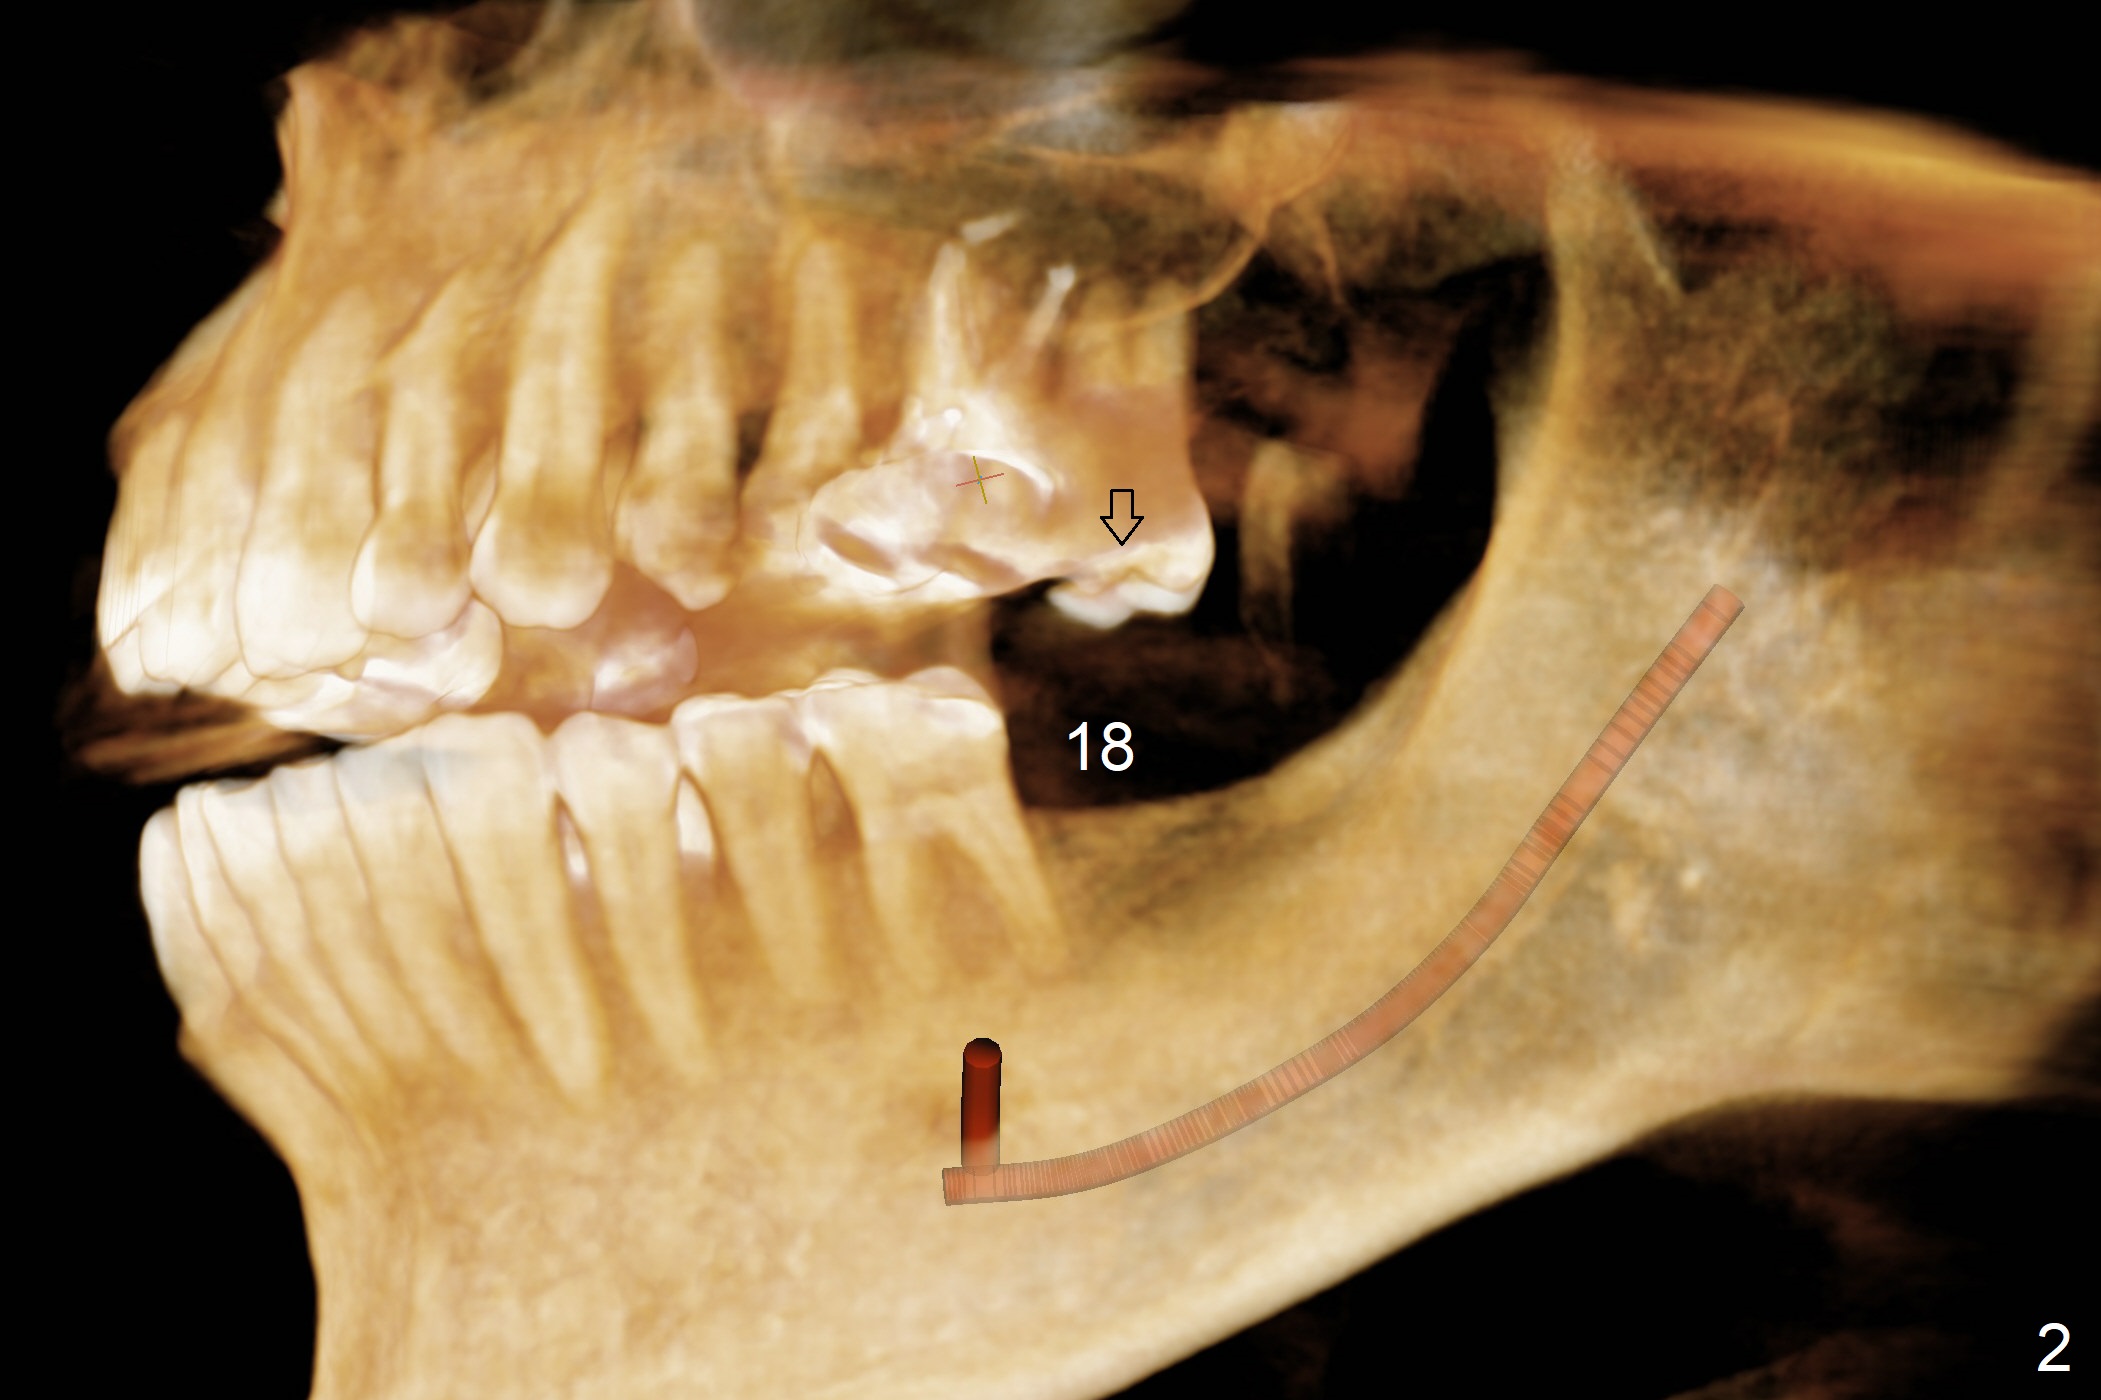

A 58-year-old man has lost the teeth #18 and 31 with supraeruption of the opposing teeth and mesial tilt of the distal tooth (Fig.1,2 arrows). Since the supraeruption is less severe on the right side (due to the presence of the tooth #32 as an antagonist to supraeruption of the tooth #2 (Fig.1' (arrow), as compared to Fig.2')), an implant will be placed at #31 with guide first (Fig.3 (coronal section of CT)). It is pity not to ask the lab to place the implant slightly distal for #32 upright. It is important to take impression for precise analysis of localized malocclusion. Intrusion of #2,15 will be initiated at the same time (Fig.4,5 (axial sections)), while the implant placement at #18 will be done last (Fig.6).